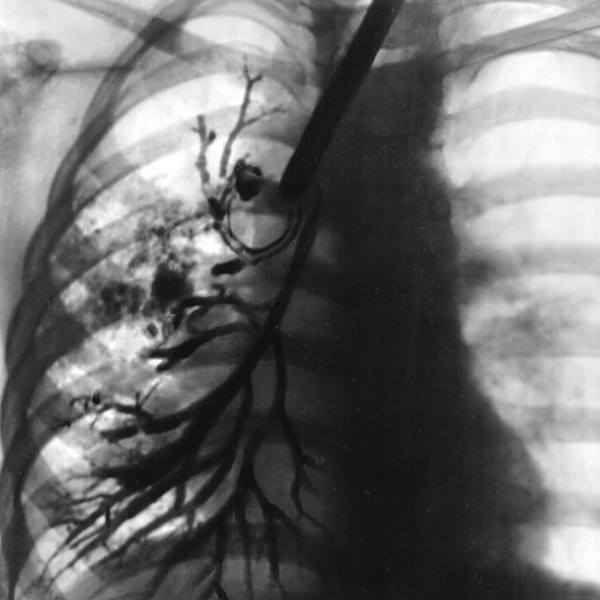

3. Бронхолегочная форма наблюдается при избыточной продукции густой слизи в респираторном тракте. Манифест заболевания часто связан с перенесенным ОРВИ. В результате повышенной плотности секрета наблюдается обструкция дыхательных путей. Нередко наблюдается вторичное инфицирование респираторного тракта. Тяжелые пневмонии, гнойно-обструктивные бронхиты имеют рецидивирующий характер, частота их возникновения достигается нескольких случаев в год. Вторичные изменения дыхательной системы проявляются эмфиземой, бронхоэктазами, пневмосклерозом, формированием легочного сердца. Вторичная инфекция чаще вызвана синегнойной палочкой, стафилококком, гемофильной палочкой или их ассоциациями. Обнаруженные микроорганизмы проявляют высокую чувствительность к распространенным антибиотикам. Наблюдается высокая летальность, обусловленная развитием дыхательной и сердечной недостаточности. На долю бронхолегочной формы отводят до 20% случае муковисцидоза.